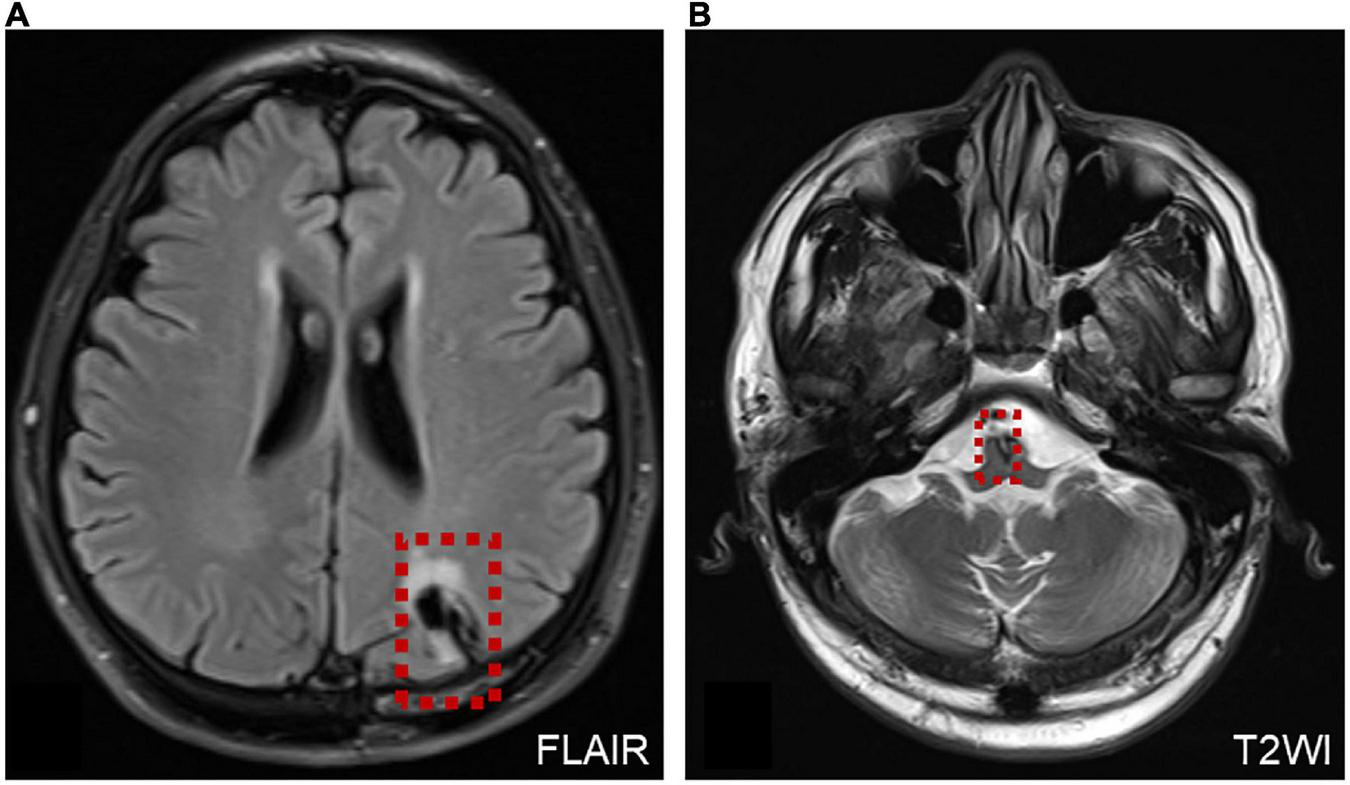

Six patients were diagnosed with posterior circulation infarction and/or ischemia, including 1 case of focal infarction of the medulla oblongata, 1 of infarction of the cochlear, and vestibular nuclei, 2 of cerebellar infarction, and 1 of extensive infarction of the brainstem and cerebellum. One patient with a focal infarction of the medulla oblongata had SN (III°), obvious oculomotor abnormalities (including gaze-evoked nystagmus; Supplementary Video 2), and abnormal saccade and pursuit. The vHIT results showed reduced VOR gains of three semicircular canals on the right side, and magnetic resonance angiography (MRA) revealed vertebrobasilar artery stenosis (Figure 3A). MRI revealed acute infarction of the right medulla oblongata, which involved the ipsilateral vestibular nucleus (Figures 3B,C). The patient with infarction of the cochlear and vestibular nuclei presented with persistent dizziness, right facial discomfort, and decreased muscle strength in the right limbs. Backward tilting was seen during the Romberg test and the Fukuda test was unstable. PTA indicated total deafness on the right side (Figure 4A). MRI showed that the infarcted focus of the right medulla oblongata near the pons involved the cochlear nucleus and vestibular nucleus (Figure 4B).

Figure 3. MRA and MRI of a patient with posterior circulation infarction. (A) MRA shows vertebrobasilar artery stenosis. (B,C) MRI shows acute infarction of the right medulla oblongata, which involved the ipsilateral vestibular nucleus (red dotted line frame).

FIGURE 4

Figure 4. Examination results of patients with infarction of the cochlear and vestibular nuclei (A,B) and right cerebellar infarction (C). (A) PTA shows total deafness on the right side in a patient with infarction of the cochlear and vestibular nuclei. (B) MRI shows that the infarcted focus of the right medulla oblongata near the pons involved the cochlear nucleus and vestibular nucleus (red dotted line frame). (C) Cranial CT and MRI of the patient with right cerebellar infarction.

Two patients were diagnosed with cerebellar lesions. One patient presented with vertigo, accompanied by gait instability, nausea, and vomiting. A physical examination and vestibular function test revealed SN to the right (II°); and positive Romberg and Fukuda tests. The caloric test and cVEMP indicated decreased vestibular function on the right side, whereas the vHIT was normal and accompanied by negative Babinski and Kernig’s signs. Cranial CT and MRI revealed a right cerebellar infarction (Figure 4C). The other patient presented with dizziness and sudden hearing loss on the right side, followed by the cerebellar herniation. Surgical treatment was applied in the Department of Neurosurgery.